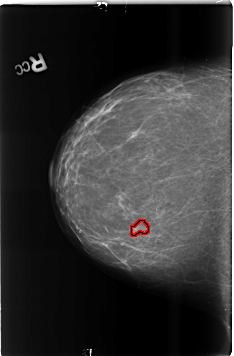

B_3482_1.RIGHT_CC

RIGHT_CC LINES 4624 PIXELS_PER_LINE 3032 BITS_PER_PIXEL 12 RESOLUTION 50 OVERLAY

FILE: B_3482_1.RIGHT_CC.OVERLAY

TOTAL_ABNORMALITIES 1

ABNORMALITY 1

LESION_TYPE MASS SHAPE LOBULATED MARGINS CIRCUMSCRIBED-ILL_DEFINED

ASSESSMENT 4

SUBTLETY 3

PATHOLOGY BENIGN

TOTAL_OUTLINES 1

BOUNDARY